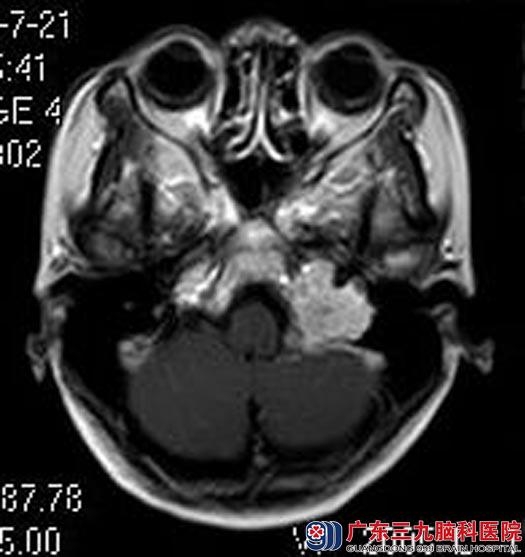

当地医院头颅CT检查提示颅内占位性病变。广东三九脑科医院头颅MR检查结果:左侧桥小脑角区占位性病变,大小约37.4mm×28.2mm×25.6mm,考虑神经鞘瘤。

▲手术前